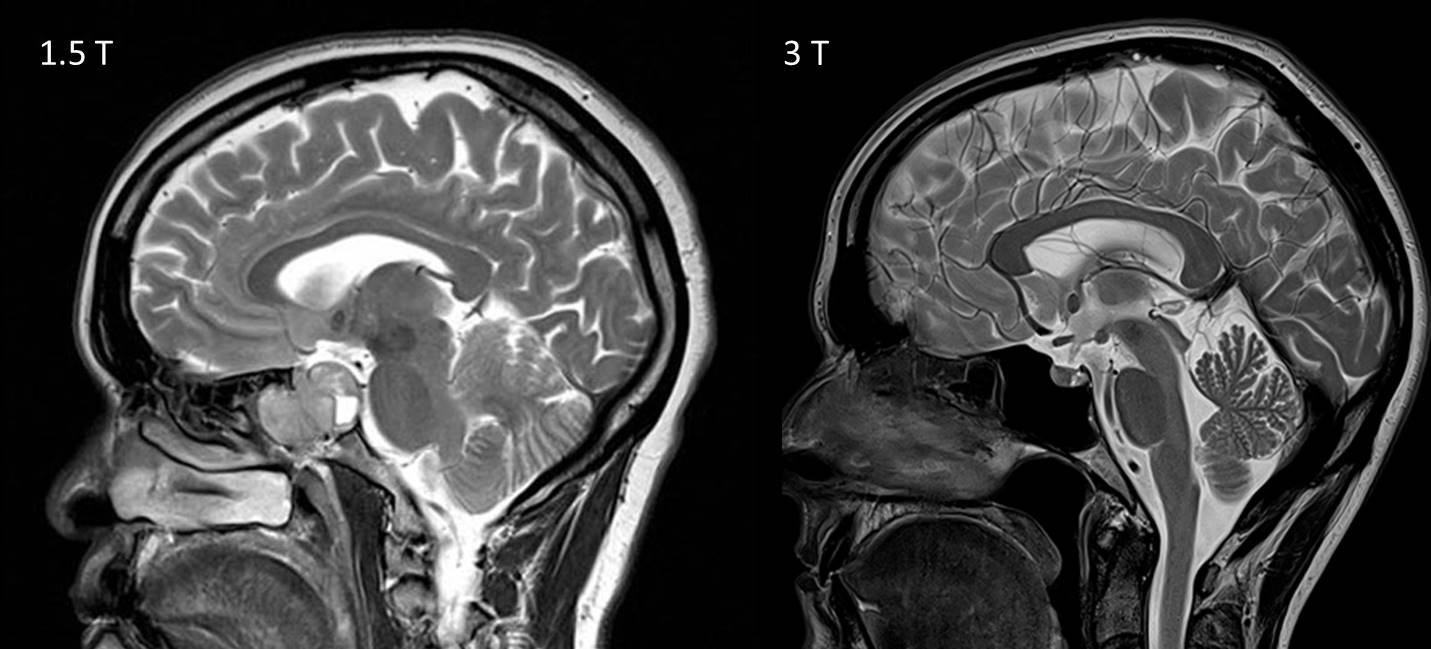

МРТ снимок головы

Сравнение снимков головного мозга методами КТ и МРТ